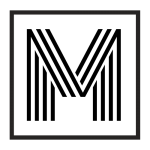

Anatomia Periodontal

Para entender sobre a importância da limpeza dental, precisamos entender um pouquinho sobre a anatomia dental e das estruturas ao redor do dente.

Ao contrário do que se pensa, o dente não está inserido diretamente em osso. Entre o osso e a raiz dental existem estruturas chamadas ligamentos periodontais, compostos basicamente por fibras de colágeno. Essas estruturas são responsáveis pela fixação dental, amortecimento da carga mastigatória e propriocepção.

A parte do dente que vemos exposta na boca é a coroa dental e, ao redor dela, temos gengiva e osso. Em situações normais a raíz dental não é visível (já que fica dentro do osso) mas em situações de retração gengival com exposição radicular isso pode acontecer.